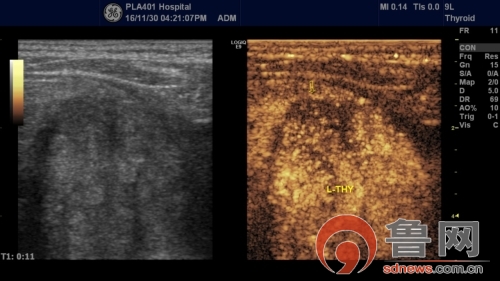

彩超引导下手术

术前患者超声造影提示为甲状腺良性肿瘤

葛现才主治医师说 :“甲状腺微波消融手术示最近新兴的手术方式,无需开刀,在彩超引导下通过消融针定向治疗病变部位,达到精准医疗,不会损伤周围组织,不仅创伤小,恢复快,住院时间短,而且可以达到美容、不留疤痕的效果,适用于病人体质差难以耐受常规手术或有美容夙愿的人群。”“此患者为老年患者,既往有多种疾病,难以耐受常规手术,且患者肿物较大、多发,位置较深,主要位于胸骨后,与周围气管、食管、神经以及血管紧密相连,手术风险大、难度高,所以术前我们反复讨论进针路径、消融步骤以及各种意外的发生做了数套应急预案,最后患者手术进行的还是很顺利的。”